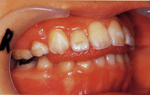

叢生(乱杭歯)気味 放置していると

放置

スペース不足で歯並びがガタガタに

叢生(乱杭歯)気味   スペース不足で歯並びがガタガタに